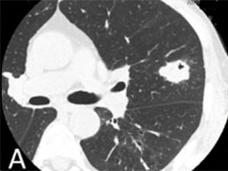

FDA Approves Alectinib for ALK-Positive Non-Small Cell Lung Cancer

The FDA has approved alectinib to treat patients with metastatic ALK-positive non-small cell lung cancer who have stopped responding to or who are unable to tolerate crizotinib.